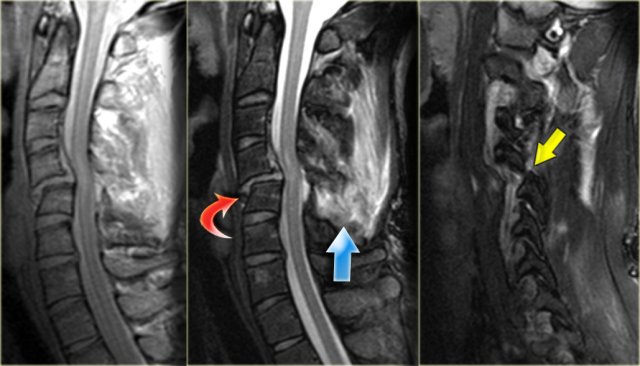

Hyperflexion sprain (3)

The MRI explains the neurological status of this patient.

The MR-findings are:

- Severe soft tissue injury of the posterior paraspinal structures, especially at the C5-6 level, where the interspinous ligament and the ligamentum flavum is ruptured

- Disruption of the C5-6 disc with migration behind C5

- Large amount of spinal cord edema

Continue with the axial image.

The axial image shows the spinal cord injury and in addition to it there is absence of flow void in the right vertebral artery.

This indicates thrombosis as a result of dissection.

In conclusion we can say that this patient had no fracture, but a severe hyperflexion sprain with acute disc herniation, non-hemorrhagic spinal cord injury and vertebral thrombosis.

The MRA confirms the occlusion of the right vertebral artery.